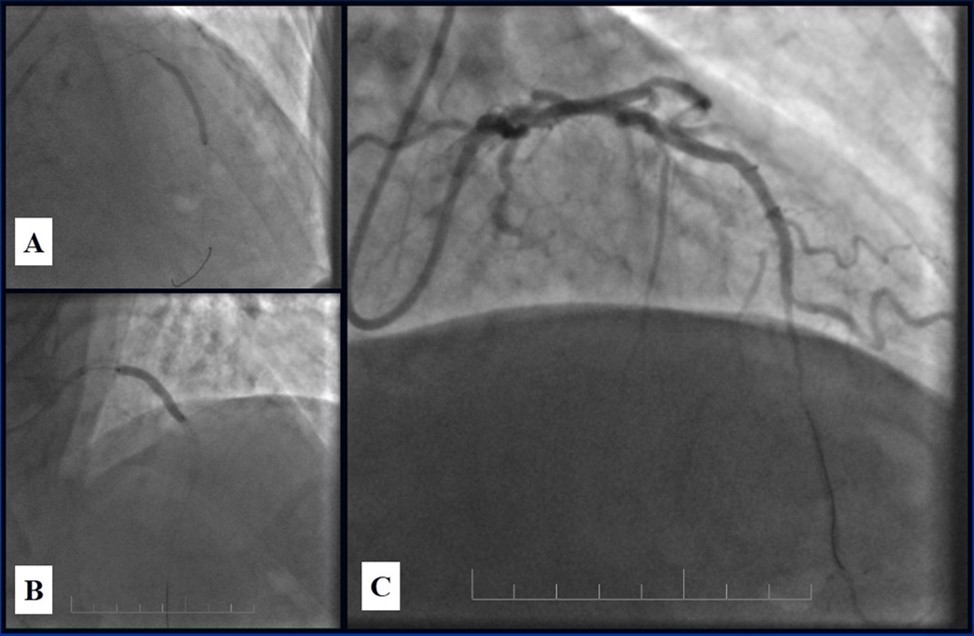

Angiography revealed rare anatomical variation LMCA quadrifurcation (Figure 1, Figure 2), 50% stenosis of the distal part of the LMCA, 40% stenosis of the ostial segment of left anterior descending (LAD) artery and diffuse prolonged 70-75-95% stenosis in mid-segment (Figure 3), 75% stenosis of the ostial segment of the circumflex (CX) artery, 75% stenosis of the ostial segment of the first marginal branch (OM1), 75-90% stenosis of the proximal segment of the intermediate artery (IMA), prolonged diffuse severe 90-95% stenosis of mid-segment of the right coronary artery (RCA) (Figure 4).

Figure 1.Quadrifurcation of the left main coronary artery

Figure 3.Prolonged diffuse severe 90-95% stenosis of mid-segment of the right coronary artery. A - Left anterior oblique 45° projection; B – Right anterior oblique 45° projection.

Figure 4.A - 50% stenosis of the distal segment of the LMCA; B - 70-75-95% stenosis in mid-segment of the LAD.